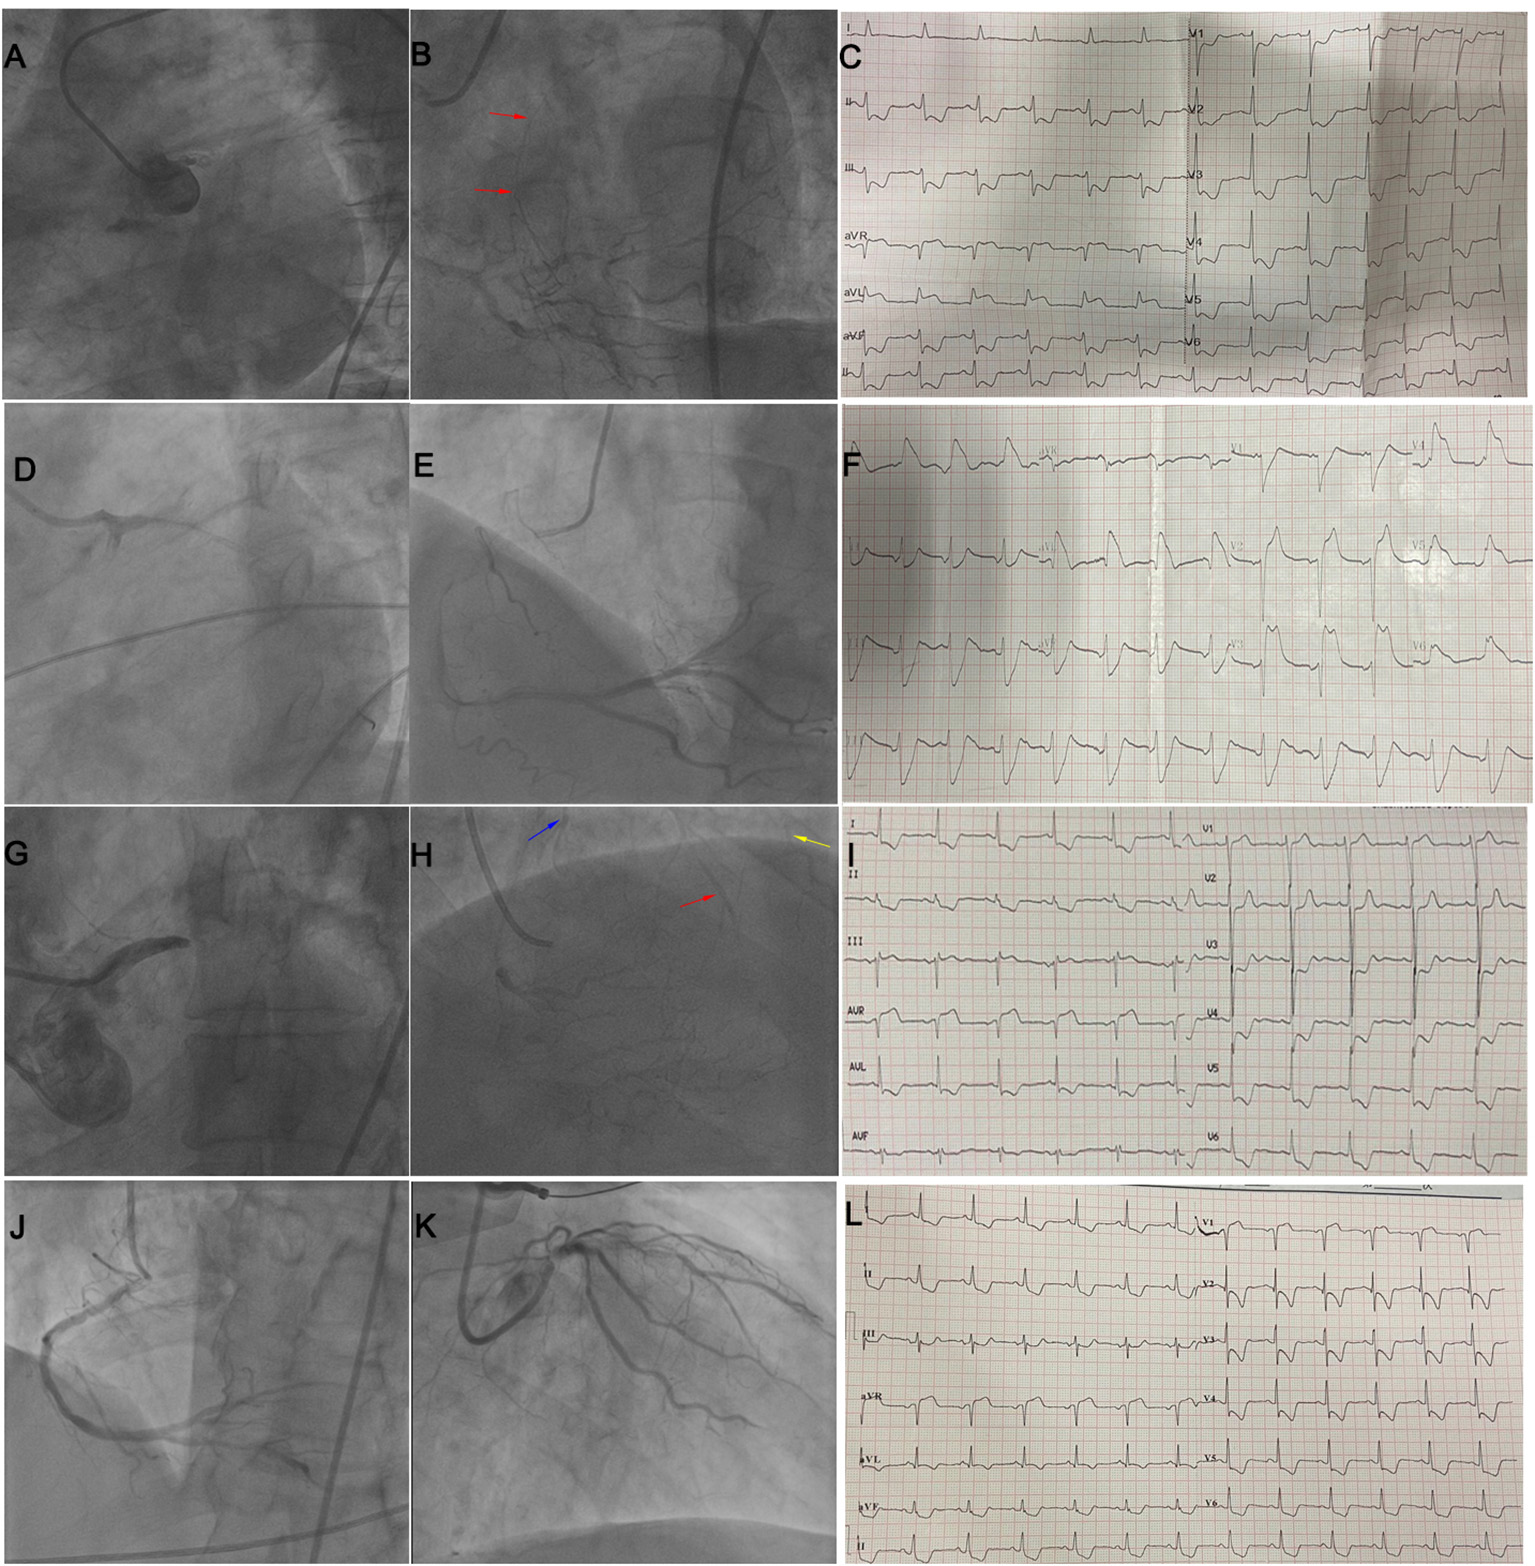

Figure 5

(A–C) illustrate STE in both leads aVR and aVL in a patient with LM occlusion and collateral filling of LAD (red arrow). (D–F) illustrate STE in I, aVL, V2–V5 in a patient with subacute stent thrombosis in LM and no collateral circulation. (G–I) illustrate STE in lead aVR in a patient with LM occlusion and collateral filling of the LAD (red arrow), diagonal branch (yellow arrow), and LCX (blue arrow). (J–L) illustrate STE in leads aVR and V1 in a patient with subtotal LM occlusion and no collateral circulation. LM, left main; STE, ST-segment elevation; LAD, left anterior descending coronary artery; LCX, left circumflex artery.